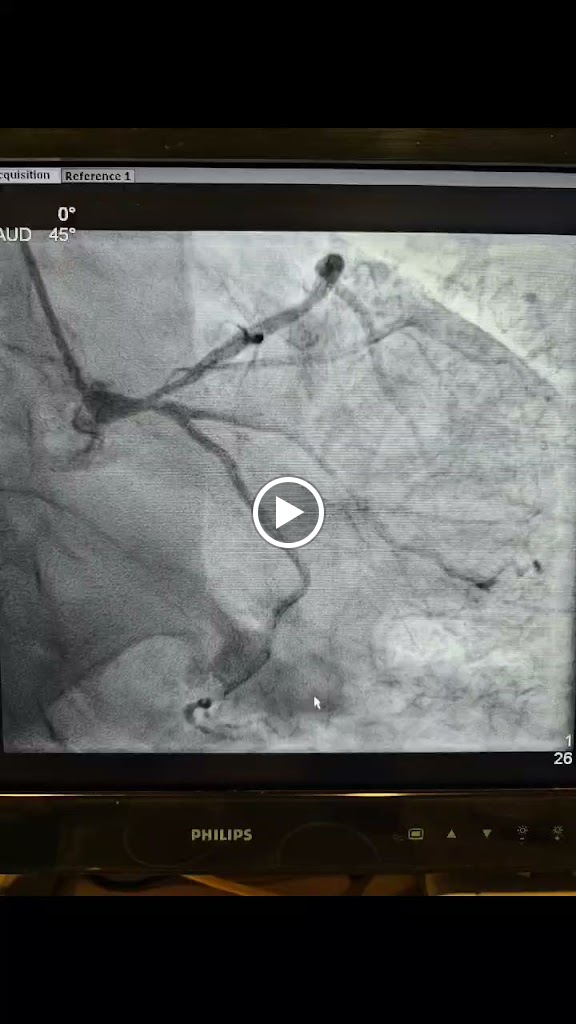

Dr. Soumya Patra is a young Cardiologist in Kolkata, who is keen to treat his patients using the Latest Techniques and Recent Advances in the field of Cardiology. He is well-versed in performing all types of Adult And Pediatric Cardiac Interventions as well as Cardiac Device Implantation (Pacemaker, CRT and ICD). He has over than 15 years of experience practicing medicine in various Hospitals and Clinics. His special interest is on Structural Heart Intervention (Trans Catheter Heart Valve Implantation and Left Atrial Appendage Closure). Peripheral Artery or Vein Intervention and Management of deep Vein Thrombosis/Pulmonary Embolism. He has published more than 100 Research Articles in various indexed journals.

He is very good. He has done my fathers CAG and PTCA in the past and very recently PPM implant. In all these procedures my father has no complain about any pain or discomfort during op or post op scenario.His behavior is very polite. I would recommend him to everyone who needs to consult a cardiologist.